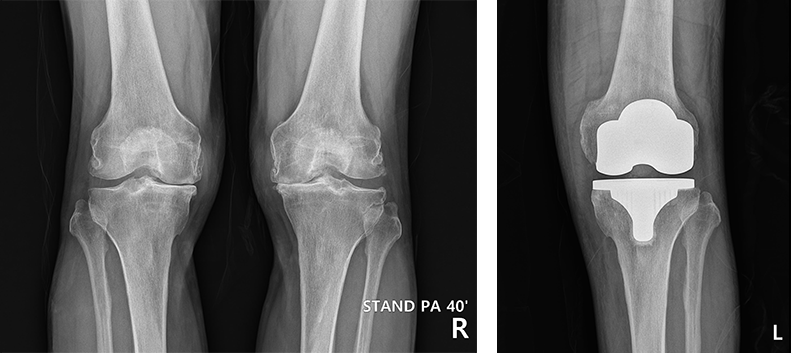

노화나 질환, 부상으로 인해 뼈의 연골과 무릎관절뼈 사이에 있는 연골이 상했을 때 인공관절로 대체해 통증을 없애고 자유로운 활동을 가능하게 하는 수술법입니다. 뼈 연골과 물렁뼈가 손상돼 다리가 휘어 있으며 통증이 있고 연골이 닳아서 정상적인 보행이 어려운 경우나 류마티스 관절염으로 관절이 많이 손상된 경우에 필요합니다.

병의 진행정도와 연령 등을 고려하여 인공관절 전체 치환술과 부분 치환술을 맞춤 적용합니다.